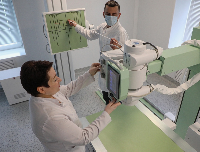

Выезд травматолога-ортопеда, рентгенолога Александра Валерьевича Дидковского.

На рабочем месте производится обучение работе на Вашем оборудовании.

Любого доктора можно быстро подготовить как рентгенлаборанта и дать необходимые знания для оценки рентгенограмм.

Изучение проблемы низкого качества рентгенограмм на Вашем оборудовании.